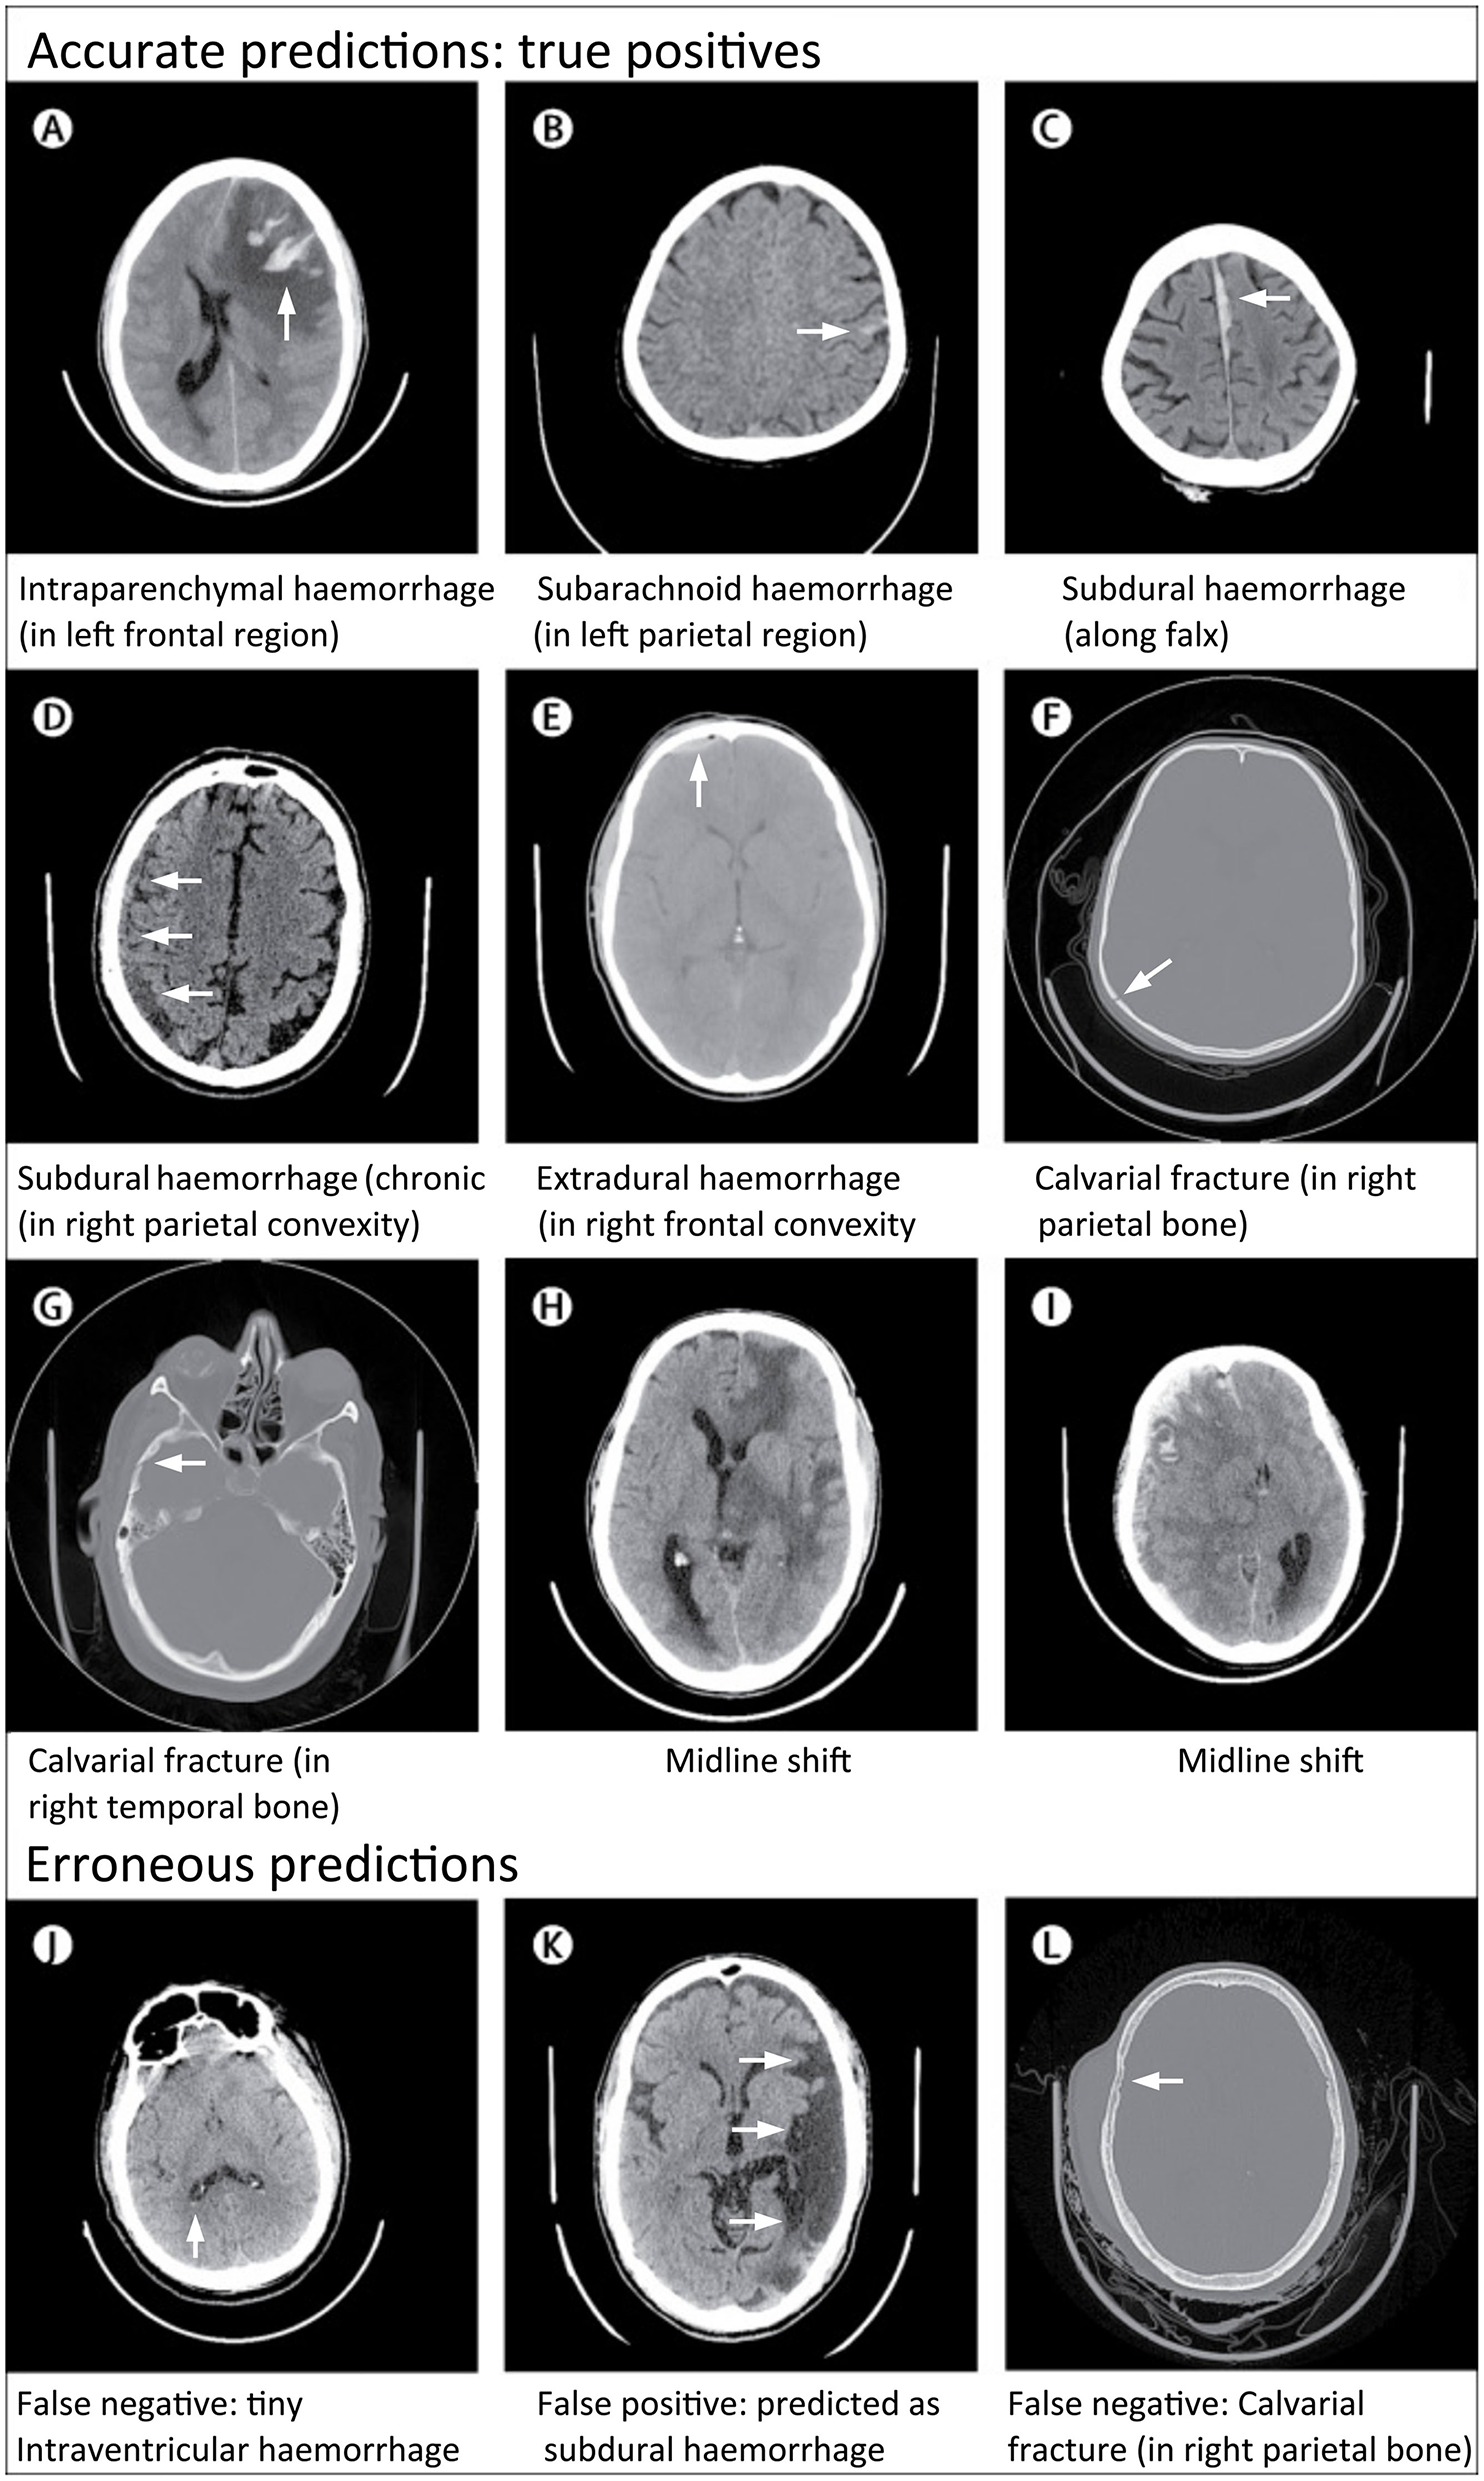

Figure 8

Examples of accurate and erroneous predictions of abnormalities on head CT in acute TBI patients by a deep learning algorithm (26). Although individual images are shown, the model classifies abnormalities at the head CT exam level. All images under Accurate Predictions (A–I) have arrows added to indicate the abnormal lesion. All images under Erroneous Predictions (J–L) have arrows added to indicate the erroneous lesion predictions.

This was the first study to evaluate model performance on individual pathologies, to use very large datasets (>100,000 CT exams), and to validate models on datasets representative of the patient population. Overall, the model performances across all pathologies were good, with the algorithm achieving an overall AUC of 0.94 for intracranial hemorrhage on CQ500. In Supplementary Materials, the authors indicated that they also trained a separate localization model to perform segmentation for intraparenchymal, subdural, and epidural hematomas, using a set of 1,706 images labeled at the pixel level according to hemorrhage subtype. Performance metrics and example images for these segmentations were unavailable at time of publication. The authors have also made the CQ500 test set publicly available to facilitate benchmarking of algorithms developed in the future.